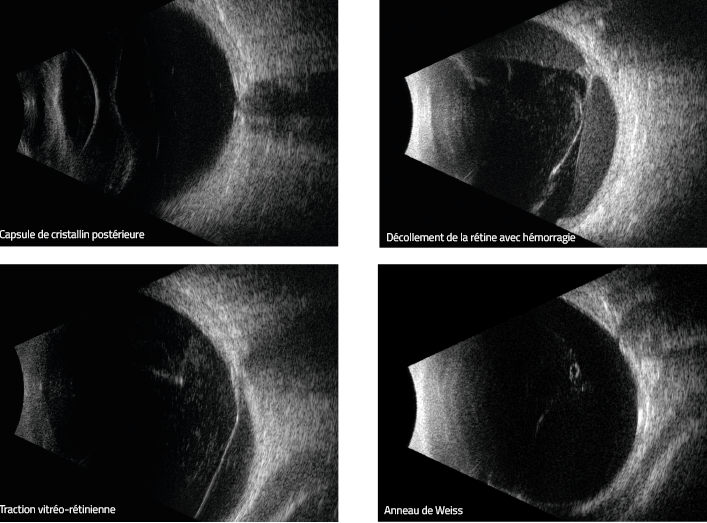

ECHOGRAPHIE OCULAIRE MODE B

Echographie de l’œil permettant d'examiner la partie postérieur de l’œil quand celui ci n'est pas analysable par le fond d'oeil